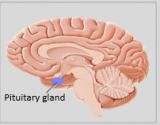

A neuroanatomia é o ramo da anatomia que estuda a anatomia do sistema nervoso, ou seja, a estrutura, a função e a organização do sistema nervoso. O sistema nervoso é um dos sistemas mais complexos do corpo humano e inclui o cérebro, a espinal medula, os nervos periféricos e os gânglios nervosos. A neuroanatomia preocupa-se com a forma como estas estruturas estão ligadas entre si, como os sinais são transmitidos entre as células nervosas e como as diferentes partes do sistema nervoso trabalham em conjunto para controlar as funções corporais e cognitivas. Os neuroanatomistas utilizam técnicas de imagiologia avançadas, como a ressonância magnética (MRI), a tomografia por emissão de positrões (PET) e a microscopia para visualizar as estruturas e funções do sistema nervoso.